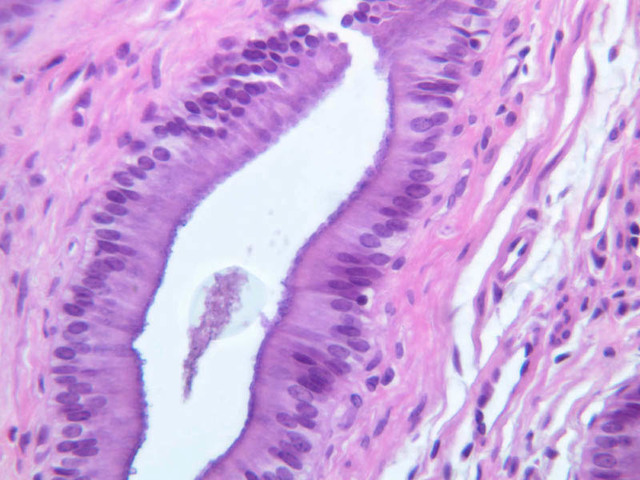

Examine the H&E-stained sections of liver (slides B-29 [10x, 20x, 40x-labeled] [2.5x-labeled, 10x, 20x, 40x] [10x-labeled, 20x, 40x-labeled] and B-30 [2.5x, 10x-labeled, 20x]). At low power, identify the connective tissue capsule (Glisson’s capsule), central veins and portal triads (portal canals). Note that the cells of the liver parenchyma (hepatocytes) appear as cords--more accurately, plates--of cells that radiate out from the central veins and partially enclose blood spaces known as hepatic sinusoids. Note that the plates of hepatocytes appear to branch and fuse and that, as a rule, they are only one or two cells thick. Do you see any binucleate hepatocytes?

Using the 10X (B-29, B-30)and 40X (B-29) objectives, examine several portal triads, noting the variable number of profiles of hepatic artery, portal vein and bile duct that comprise the portal triad. Near the boundary between adjacent lobules, try to find some of the small elements of the bile duct system known as canals of Hering.

Using the high dry objective, study the lining of the central vein and hepatic sinusoids (B-29). In some places the hepatocytes are exposed directly to the sinusoidal lumen, but, as a rule, there is a basal lamina which supports a discontinuous mosaic of endothelial cells and specialized phagocytic cells known as Kupffer cells. Find examples of Kupffer cells and endothelial cell nuclei. Note that in some places you may see a narrow space (the space of Disse) between hepatocytes and the basement membrane underlying endothelial and Kupffer cells. Using the oil immersion (100X) objective, look very carefully along the boundaries between adjacent hepatocytes to see if you can find a bile canaliculus--the most delicate portion of the bile duct system--the walls of which are formed by the plasma membranes of adjacent hepatocytes.